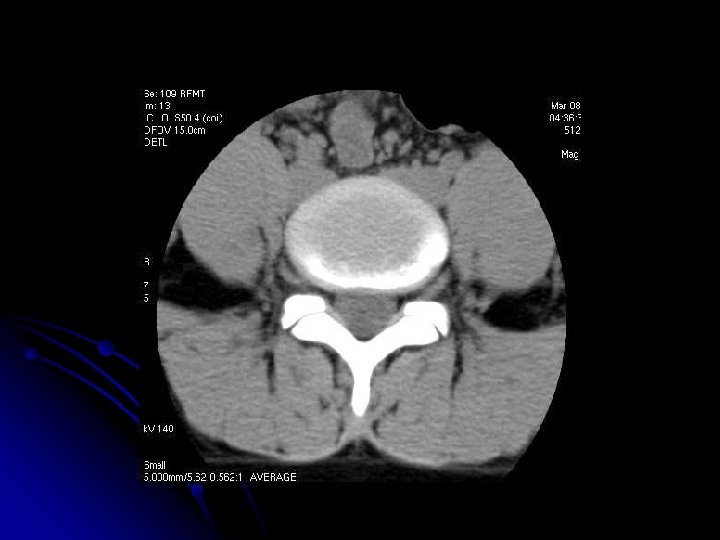

TOMODENSITOMETRIE

2. Choix des paramètres d'acquisition

l Epaisseur des coupes: 3 mm ++ l Coupes jointives ou chevauchées: excellente qualité de reconstructions

l Reconstructions 2 D : l Recherche d'un fragment discal migré sur des reconstructions sagittales, l Appréciation de la liberté des foramens sur des reconstructions sagittales obliques dans un bilan de hernie ou de tumeur, l Etude du mur postérieur et du canal rachidien dans un contexte traumatique, dans plusieurs plans, l Correction du plan axial transverse en cas de scoliose. . .

l Rachis dorsal l Le mode radio devra être réalisé avec un champ suffisant pour compter les vertèbres par rapport au sacrum. l Rachis lombaire l La progammation des coupes dépend de l'indication si on n'utilise pas le mode hélicoïdal : l Dans le plan des disques: disques, corps vertébraux, et espace périrachidien ; l Dans le plan des isthmes: l'arc postérieur et en particulier les lyses isthmiques